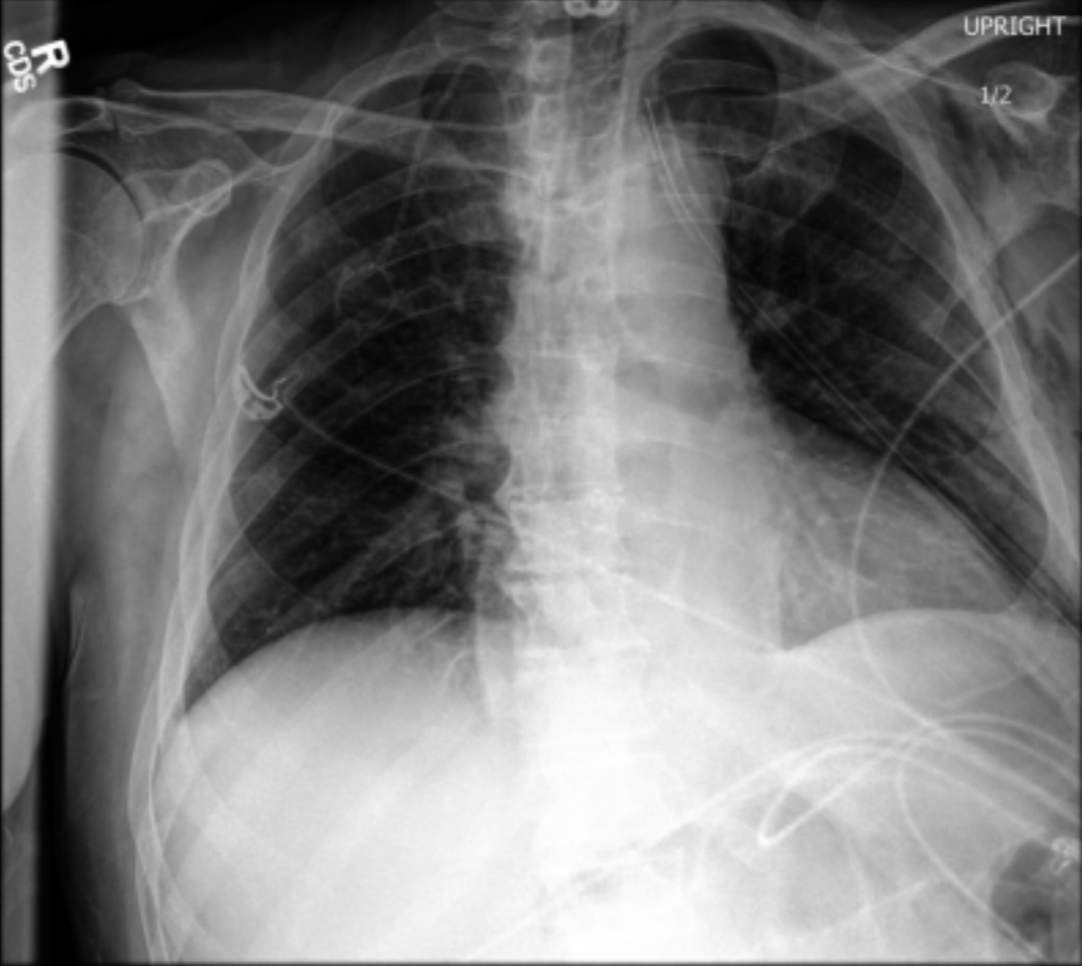

Firstly, we evaluate RadVLM on a core radiology task: generating a textual report from a frontal CXR. As our evaluation set, we use a filtered version of the MIMIC-CXR test set, excluding statements about findings from prior examinations. We report in Table 3 both lexical (BertScore, Rouge-L) and clinical (RadGraph F1, GREEN) metrics, which capture different performance aspects of the report generation task.

As mentioned in Section 4.2, five additional VLMs – including three specific to CXR (RaDialog, CheXagent, MAIRA-2) – are also evaluated, with minor adaptations to each model’s recommended prompt template (Appendix 1-Table 2). Many of these models were originally evaluated under different conditions (sometimes benefiting from extra inputs like prior images/reports or patient details or omitting certain metrics such as GREEN). To ensure that our setup remains consistent across all of them, we apply the same evaluation pipeline (test set and metrics).

For non-CXR specific VLMs, we observe a poor performance in both lexical and clinical metrics, with an unexpected improved performance for the generalist model (LLaVA-OneVision) over the medical one (LLaVA-Med), presumably profiting from a better architecture and training process (Li et al.,, 2024). CXR-specific models perform significantly better than generalists, with a notable advantage of CheXagent in terms of clinical metrics. Although MAIRA-2 was reported to excel in report generation (Bannur et al.,, 2024), we note that it was trained using additional inputs (indications, prior images, lateral views) that are not provided in our single‐image setup; thus, its lower performance here does not fully reflect its full capabilities. Overall, RadVLM achieves competitive results, attaining the highest performance in lexical metrics and the second-best in clinical metrics. This validates our approach, even though our training methodology was not specifically designed for the report generation task.